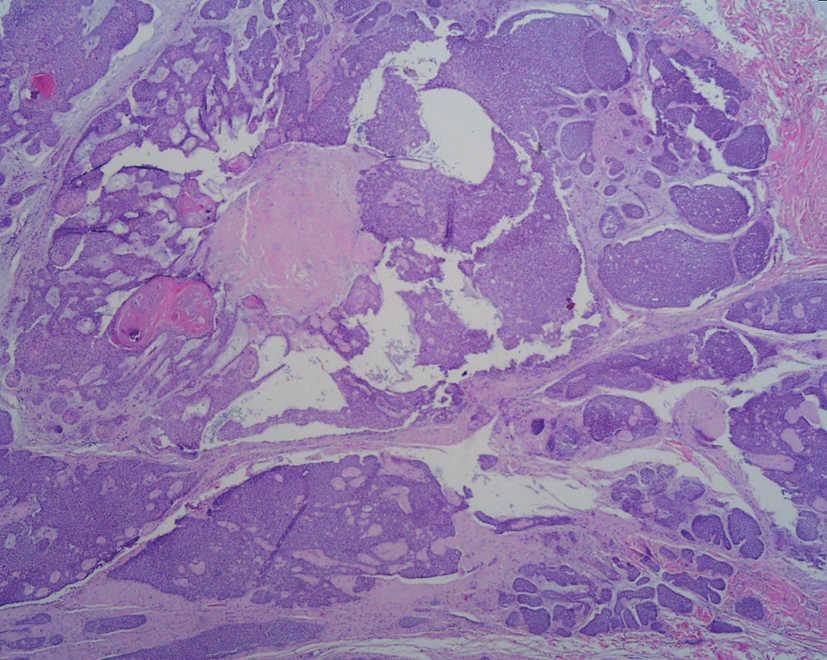

El estudio histopatológico puso de manifiesto una tumoración formada por varios nódulos dérmicos, de distintos tamaños, con componentes sólidos y quísticos (fig. 2). Las áreas sólidas estaban formadas mayoritariamente por células poroides basófilas, de núcleo redondeado u oval, con escaso citoplasma y aisladas formaciones ductales interpuestas (fig. 3).

Fig. 2.--Tumoración formada por varios nódulos dérmicos, con componentes sólidos y quísticos. (Hematoxilina-eosina, x4.)